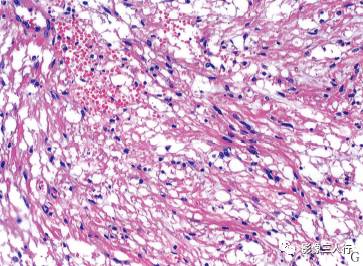

(四)病理诊断

“第四脑室肿瘤小脑白质内毛细胞型星形胶质细胞瘤(图G)。